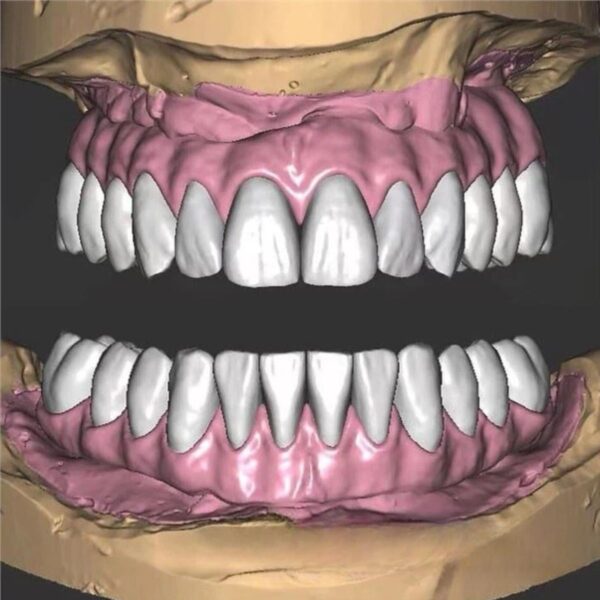

Dental Inlay CAD Design Service (Class I, II & MOD)

Conservative designs with perfect internal adaptation.

- Scope: Class I, Class II (MO/DO), and MOD Inlays.